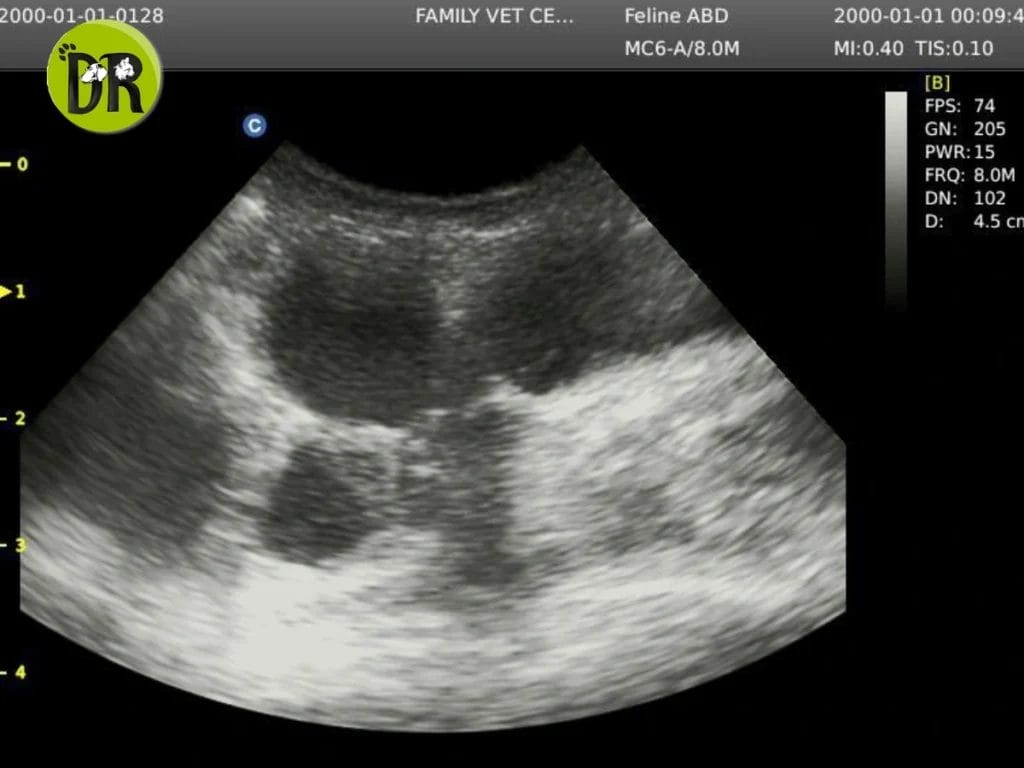

أظهر الفحص وجود انتفاخ في البطن، وأكد التصوير بالأشعة فوق الصوتية وجود مشكلة في الرحم أدت إلى تجمع السوائل، وهو ما يفسر القيء المتكرر وسلوك الانعزال.

ساعدت الأشعة فوق الصوتية الدقيقة في تحديد سبب الترجيع وتخطيط الجراحة بأمان، تحت إشراف Dr. Ahmed Baher.